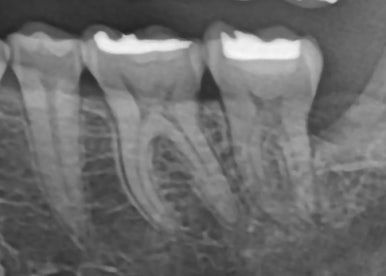

✅ 실제 치료 케이스 1: 좌측 어금니 #37 C-shape canal

- 환자 증상: 가만히 있어도 욱신, 씹을 때 통증

- 검사 결과: 크랙과 치수염 진행, 신경치료 필요

📸 러버댐 장착 후 C형 근관 확인

→ 내부에 여러 갈래로 연결된 신경관 존재